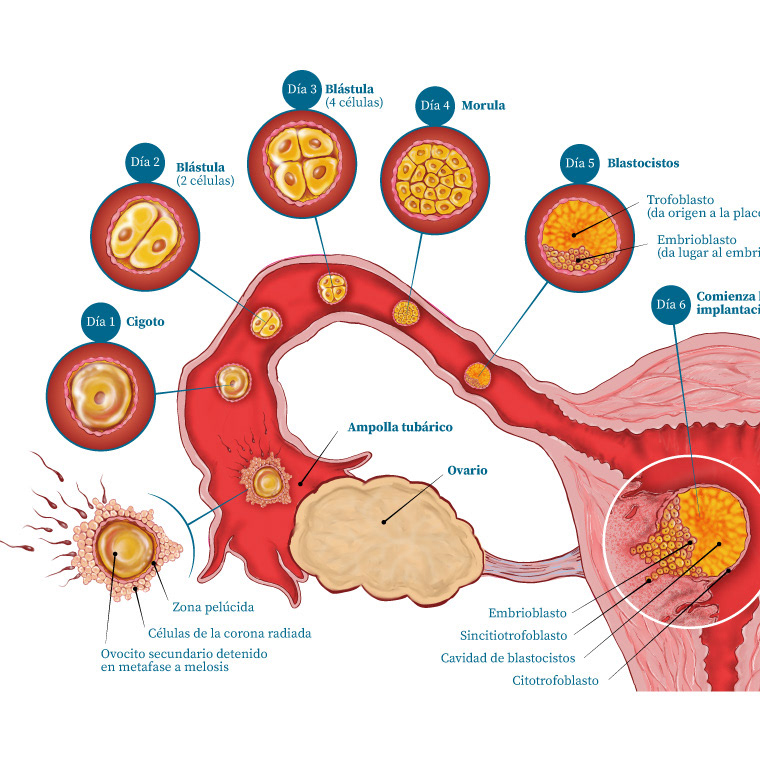

Ilustración médica / Ginecología

Infografía / Ginecología